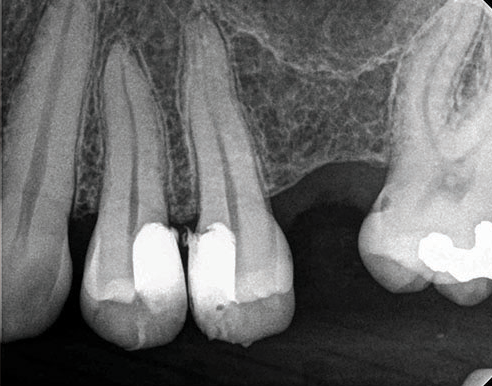

(7.) One-year follow-up periapical and bitewing radiographs demonstrating the absence of apical pathosis or furcal pathosis at the site of

the perforation.

Figure 7

(8.) One-year follow-up periapical and bitewing radiographs demonstrating the absence of apical pathosis or furcal pathosis at the site of

Figure 8